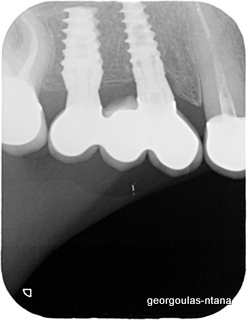

ΠΡΟΣΘΕΤΙΚΗ ΑΠΟΚΑΤΑΣΤΑΣΗ ΣΤΗΝ ΑΝΩ Κ ΚΑΤΩ ΓΝΑΘΟ ΚΑΙ ΤΟΠΟΘΕΤΗΣΗ ΕΜΦΥΤΕΥΜΑΤΩΝ ΜΕ ΚΛΕΙΣΤΗ ΑΝΥΨΩΣΗ ΙΓΜΟΡΕΙΟΥ

περισσότερα...